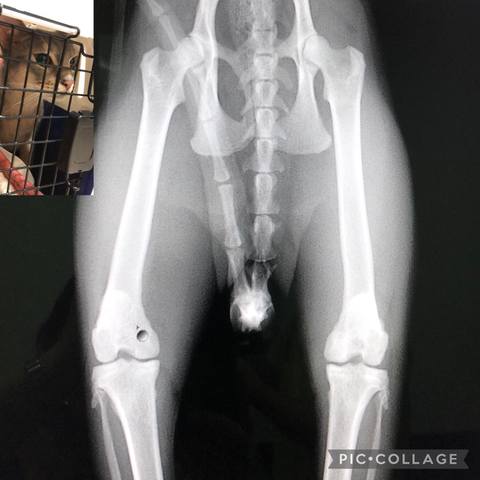

らるたん健康記録

通院記録とか、体調のこととかニャ😽